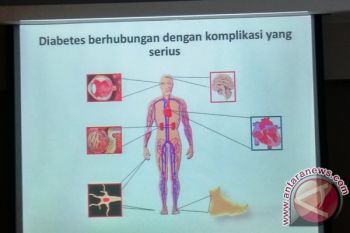

Salah satu risiko kesehatan yang bisa menghantui penderita diabetes adalah terkena masalah seksual seperti disfungsi ...

Terkadang seseorang tak menyadari kalau dirinya menyandang diabetes karena gejala yang muncul bisa saja tak terasa. ...